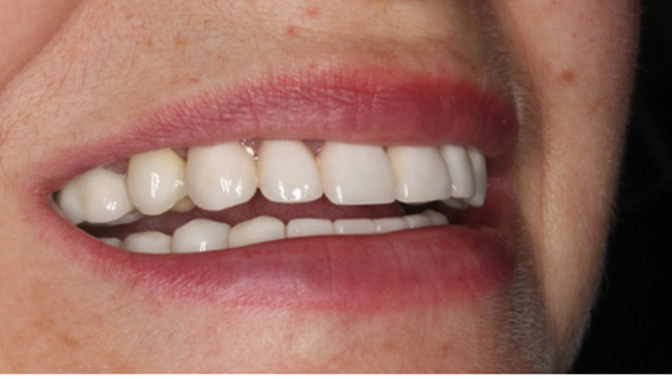

“Patient’s smile was recovered on the day of surgery

with reliable & highly-aesthetic results using AnyRidge & R2GATE. ”

Clinical case: AnyRidge immediate loading

- Courtesy of Dr. Andres Paraud Freixas, Chile -

AnyRidge, ISQ value, initial stability, immediate loading, KnifeThread, maxillary anterior, Mega ISQ, Dr. Andres Paraud Freixas

AnyRidge implant system, Mega ISQ, Digital prosthesis